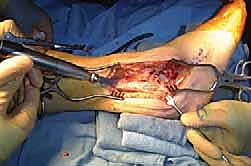

خطوات العملية الجراحية بالتفصيل: رحلة داخل غرفة العمليات

إجراء "Tibiotalocalcaneal Arthrodesis" هو عمل فني هندسي يتطلب دقة متناهية. يستغرق الإجراء عادة من ساعتين إلى ثلاث ساعات، ويتم تحت التخدير النصفي أو العام. إليك الخطوات التي يتبعها الأستاذ الدكتور محمد هطيف لضمان نجاح العملية:

الخطوة الأولى: التحضير والنهج الجراحي

يتم وضع المريض على جانبه أو على ظهره مع وضع وسادة تحت الورك لتدوير الساق للداخل. يتم استخدام عاصبة (Tourniquet) لوقف تدفق الدم مؤقتاً لضمان رؤية واضحة خالية من النزيف. يقوم الدكتور هطيف بعمل شق جراحي على الجانب الخارجي للكاحل (Lateral Approach). غالباً ما يتم قطع جزء من عظمة الشظية (Fibula) واستخدامها لاحقاً كطُعم عظمي.

الخطوة الثانية: تجهيز الأسطح المفصلية (Preparation)

هذه هي الخطوة الأكثر أهمية. يقوم الجراح بفتح مفصل الكاحل والمفصل تحت الكاحل وإزالة كل ما تبقى من الغضاريف التالفة والأنسجة الميتة. الهدف هو الوصول إلى "العظم الإسفنجي النازف" (Bleeding Cancellous Bone). العظام الميتة لا تلتئم؛ يجب أن يكون السطح غنياً بالخلايا الجذعية والتروية الدموية. يتم استخدام أدوات دقيقة، وأحياناً المناظير، لضمان إزالة الغضروف بالكامل دون إزالة الكثير من العظم الأساسي.

الخطوة الخامسة: تركيب صفيحة الشفرة الجانبية

يتم تشكيل الصفيحة المعدنية (المصنوعة من التيتانيوم أو الفولاذ المقاوم للصدأ الطبي) لتطابق الانحناء التشريحي لساق وقدم المريض. يتم إدخال "الشفرة" الخاصة بالصفيحة بدقة في عظمة الكعب (Calcaneus). ثم يتم تثبيت الجزء العلوي من الصفيحة على عظمة الساق (Tibia) باستخدام مسامير قوية.

الخطوة السادسة: الضغط النهائي والتثبيت

باستخدام أداة شد خاصة، يقوم الجراح بسحب الصفيحة لتوليد ضغط ميكانيكي هائل على المفاصل المجهزة. هذا الضغط يغلق أي فجوات ويضمن تلامساً محكماً بين العظام. يتم إضافة مسامير إضافية تعبر المفاصل (Lag Screws) لزيادة الثبات.